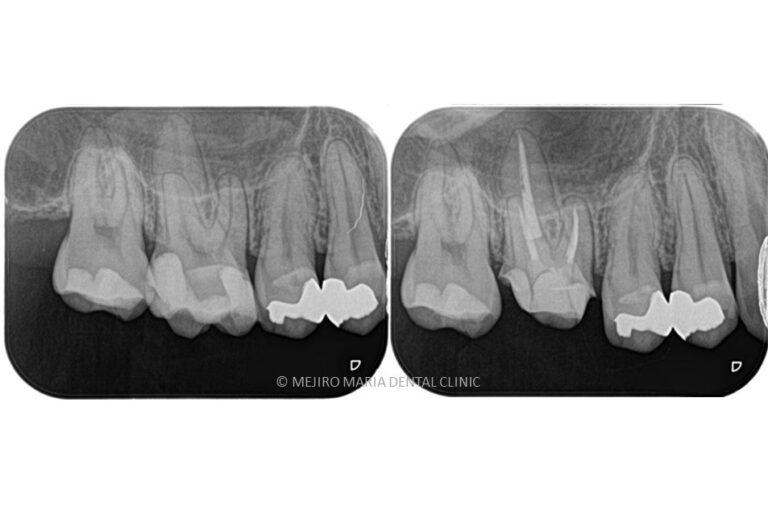

【初回根管治療(抜髄)神経をとる

治療】

初めて歯の神経(歯髄)を取り除く処置です。歯髄炎の症状は抜髄処置を施すことで改善されます。また、根管内の細菌感染が再根管治療よりはまだ少ないので、治療の成功率が高い時期でもあります。根尖性歯周炎の罹患を最小限にすると同時に再根管治療を不要にすることで将来的に歯を最大限保存することにつながるため、再根管治療に比べると精密根管治療の費用対効果が高くなります。

【再根管治療(感染根管治療)】

感染した歯髄や腐敗物、細菌を取り除く治療

再根管治療とは、過去に行った根管治療のやり直しを行う処置です。根尖性歯周炎の原因は根管内に潜む細菌感染ですので、根管内の細菌数を無菌的環境下で減少させ、密に封鎖することで予知性を高めることが可能です。